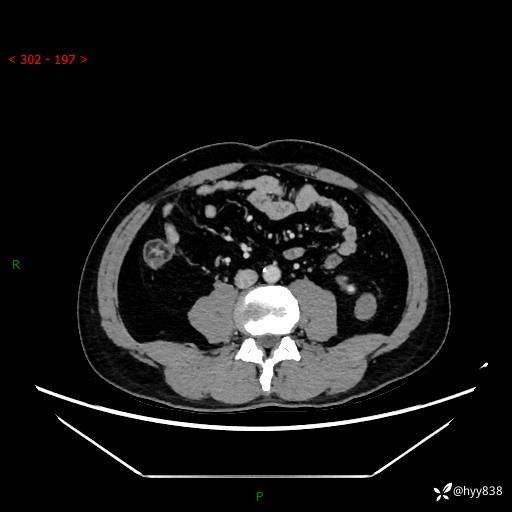

中年男性,左侧腰背部间断性胀痛不适。第一眼“乳头或囊肿”,有无意外---(有结果)

【患者信息】:41岁/男

【主诉】:左侧腰背部间断性胀痛不适1周

【现病史及既往史】:患者1周前无明显诱因出现左侧腰部疼痛,呈间断性胀痛,休息后可缓解,无放射痛,偶可见肉眼血尿,无血块,无尿频尿急尿痛,无夜尿增多,无畏寒发热、咳嗽咳痰等症状。于我院查双肾CT示:左肾占位性病变,左肾下极囊性病变,左肾轻度积水,胆囊多发结石。今为求进一步诊治来我院,门诊以“左肾占位性病变”收治入院。 起病以来,患者精神佳,饮食、睡眠良好,大便正常,小便如上诉,体力体重无明显变化。

【检查】:肾脏CT平扫+增强